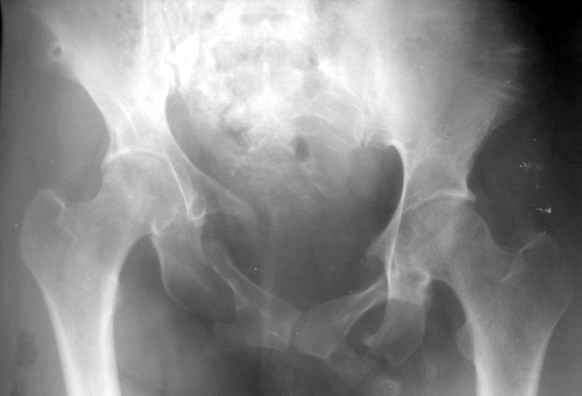

Привожу пример лечения больного с 7 месячной деформацией. Отеотомии - аппарат - внутренняя фиксация.

Рентгенограммы до и через месяц после окончательной стабилизации. Потом поищу более поздние снимки.